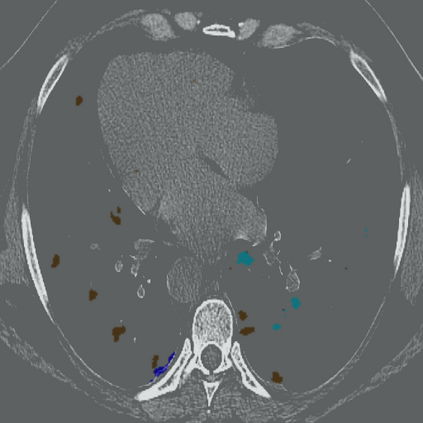

The novel coronavirus disease 2019 (COVID-19) has been spreading rapidly around the world and caused significant impact on the public health and economy. However, there is still lack of studies on effectively quantifying the lung infection caused by COVID-19. As a basic but challenging task of the diagnostic framework, segmentation plays a crucial role in accurate quantification of COVID-19 infection measured by computed tomography (CT) images. To this end, we proposed a novel deep learning algorithm for automated segmentation of multiple COVID-19 infection regions. Specifically, we use the Aggregated Residual Transformations to learn a robust and expressive feature representation and apply the soft attention mechanism to improve the capability of the model to distinguish a variety of symptoms of the COVID-19. With a public CT image dataset, we validate the efficacy of the proposed algorithm in comparison with other competing methods. Experimental results demonstrate the outstanding performance of our algorithm for automated segmentation of COVID-19 Chest CT images. Our study provides a promising deep leaning-based segmentation tool to lay a foundation to quantitative diagnosis of COVID-19 lung infection in CT images.

翻译:2019年新的冠状病毒疾病(COVID-19)在全世界迅速蔓延,对公共卫生和经济产生了重大影响;然而,对于有效量化COVID-19造成的肺感染,仍然缺乏研究;作为诊断框架的一项基本但具有挑战性的任务,分解在通过计算断层摄影(CT)图像测量的COVID-19感染的准确量化方面发挥着关键作用;为此,我们提出了对多个COVID-19感染区域进行自动分解的新型深层次学习算法。具体地说,我们利用综合残余变异学来学习一种稳健和直观的特征表征,并运用软关注机制来提高模型的能力,以区分COVID-19的症状。用公共CT图像数据集,我们验证了拟议的算法与其他相竞方法的功效。实验结果表明,我们自动分解COVID-19 Chest CT 图像的算法表现出色。我们的研究提供了一个充满希望的深度精细分解工具,为CT 图像中COVID-19肺感染的定量诊断奠定了基础。